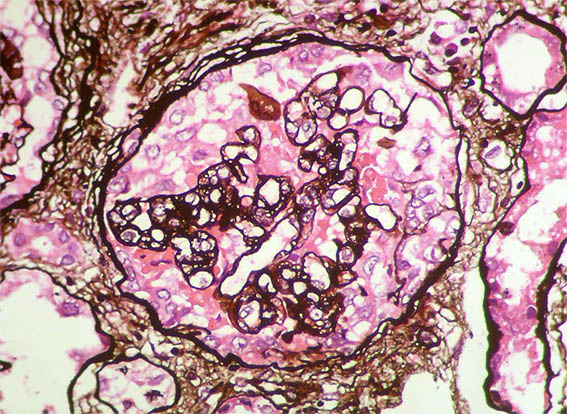

Figura 7. Plata-metenamina, X400. Dobles contornos. Semiluna versus hiperplasia severa de podocitos.

Figura 8. Plata-metenamina, X400. Patrón de membranoproliferativa y pequeña semiluna en la parte superior.